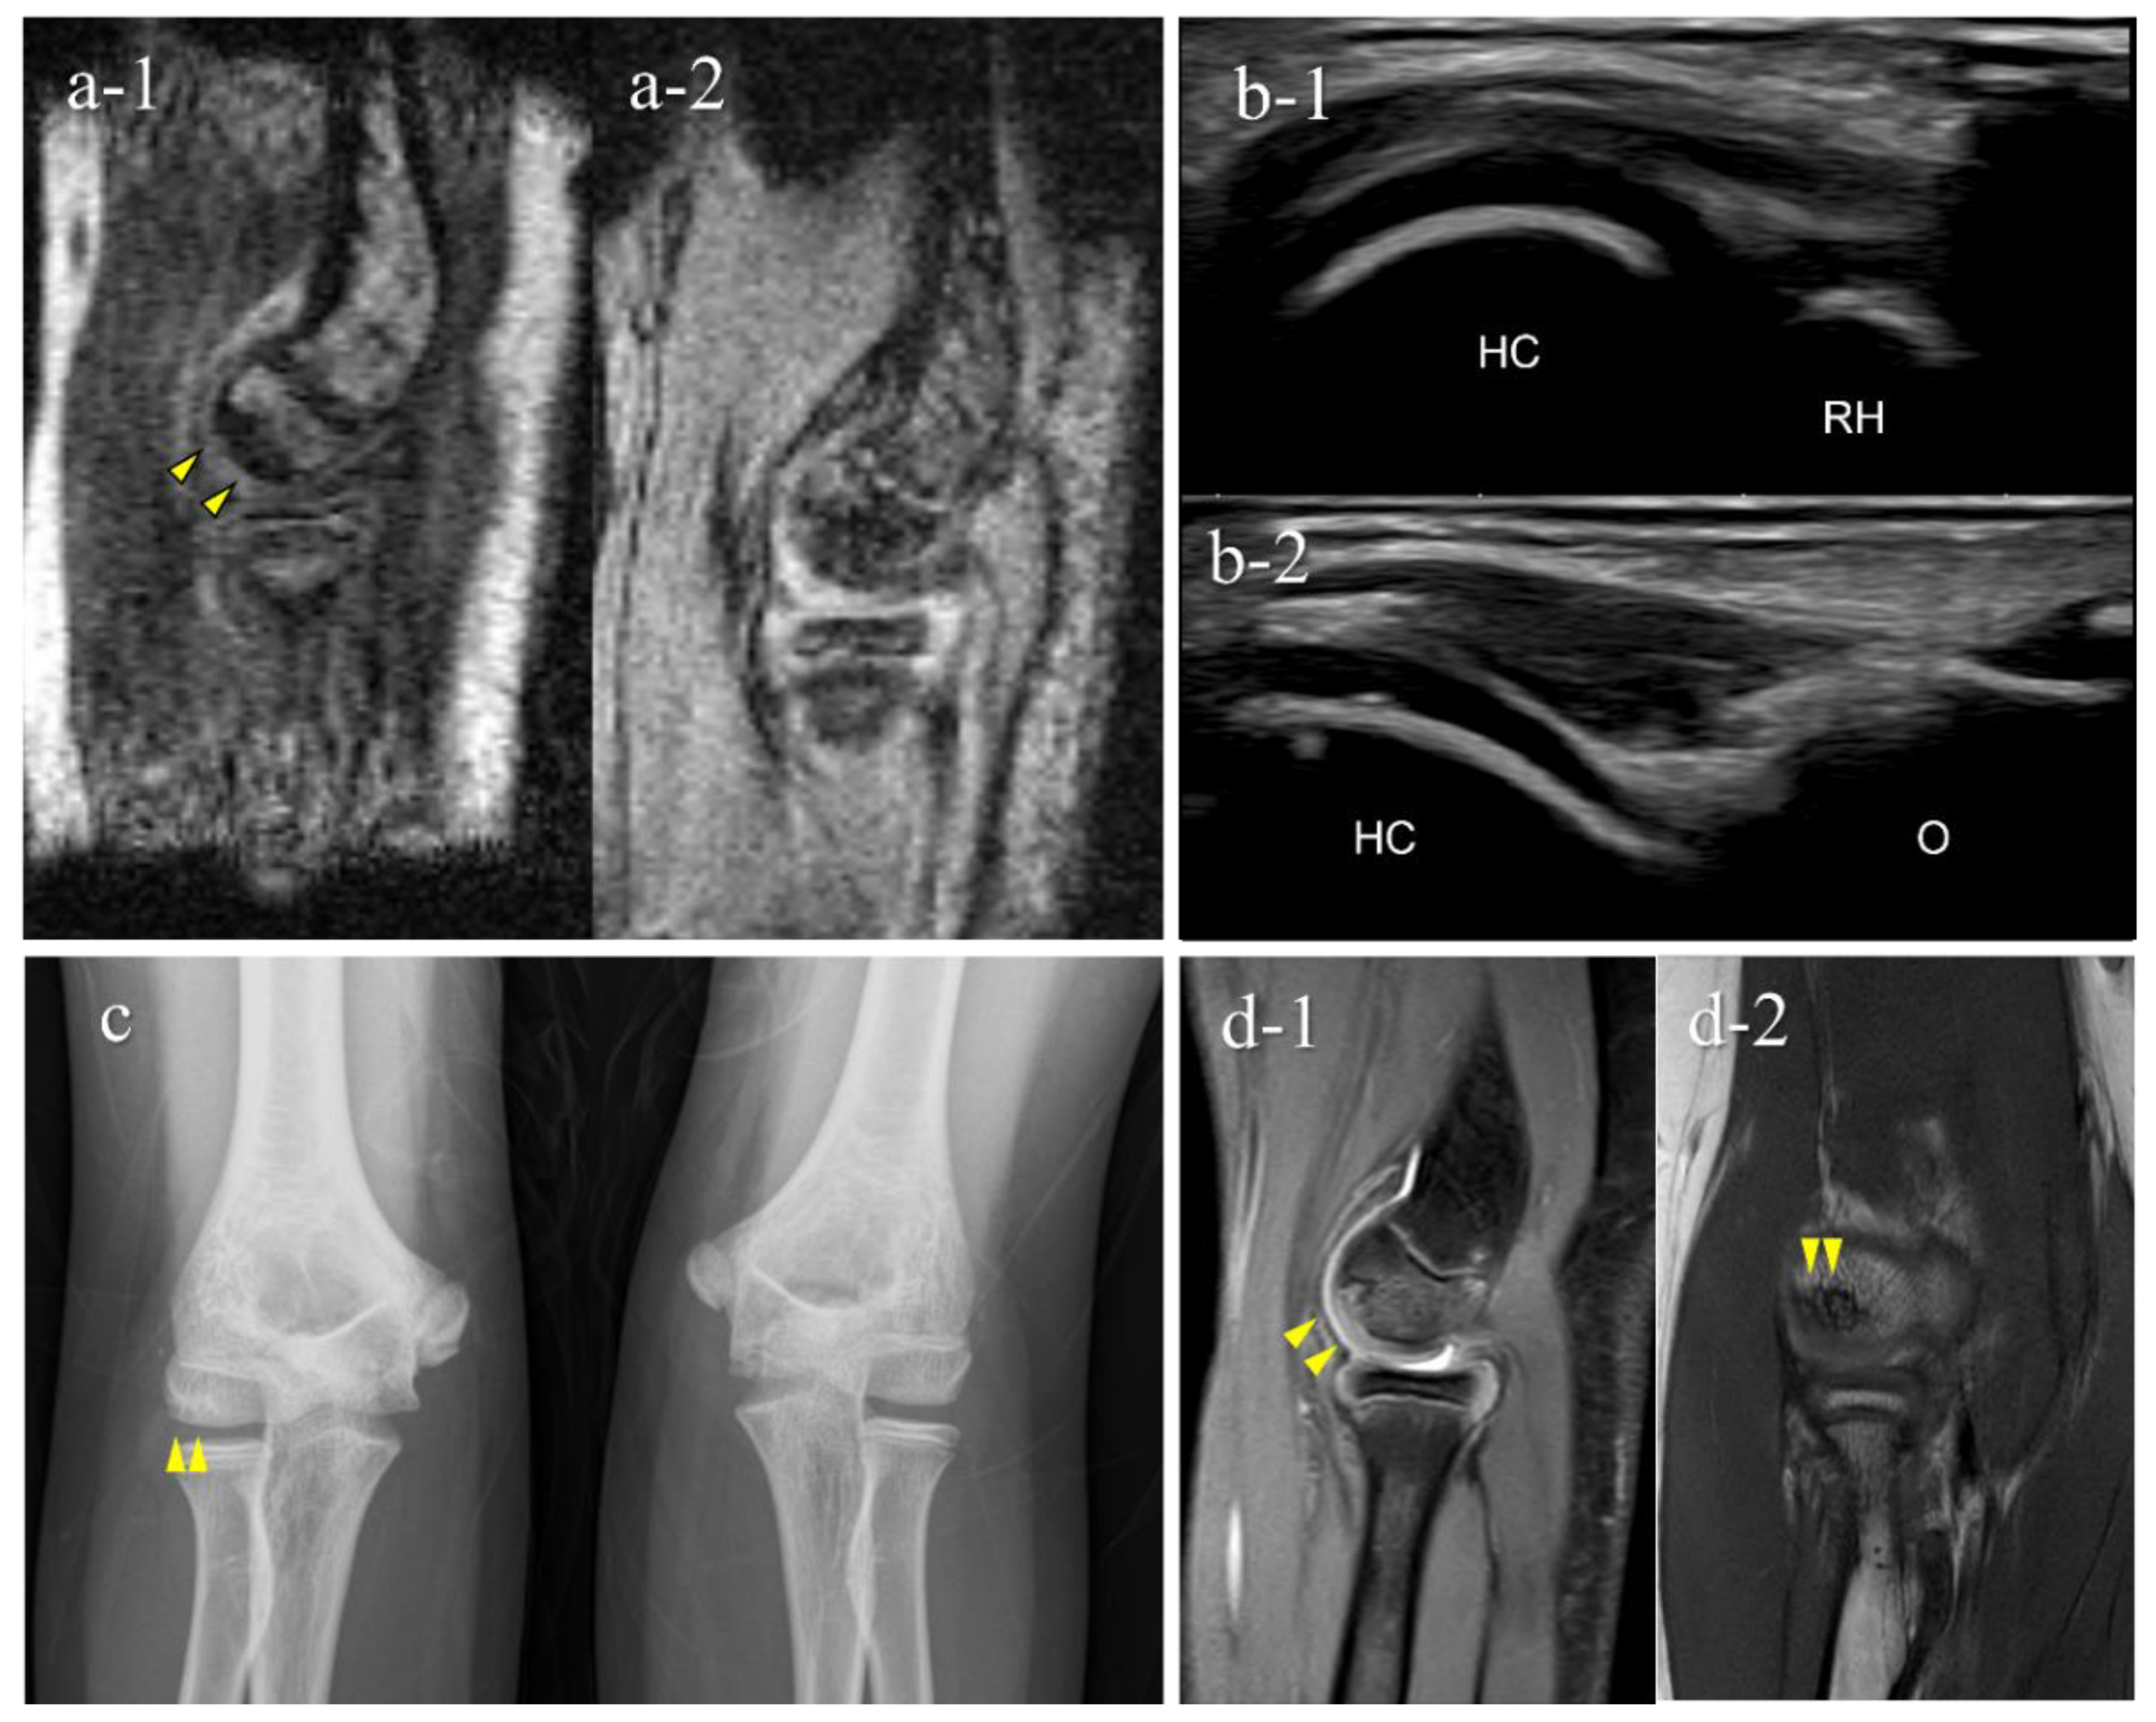

| 1 | 12 | M | - | − (1st) | + (B) | OCD | II | lateral | 15 |

| 2 | 11 | M | + | + (1st) | + (B) | OCD | I | central | 10 |

| 3 | 12 | M | - | + (2nd) | + (B) | OCD | II | central | 9 |

| 4 | 12 | M | + | + (2nd) | + (B) | OCD | II | lateral | 11 |

| 5 | 12 | M | + | + (2nd) | − (B) | OCD | I | central | 3.5 |

| 6 | 15 | F | - | + (2nd) | − (C) | not OCD | posterior | 3.5 | |

| 7 | 12 | M | - | + (2nd) | − (D) | OCD | I | central | 5.5 |